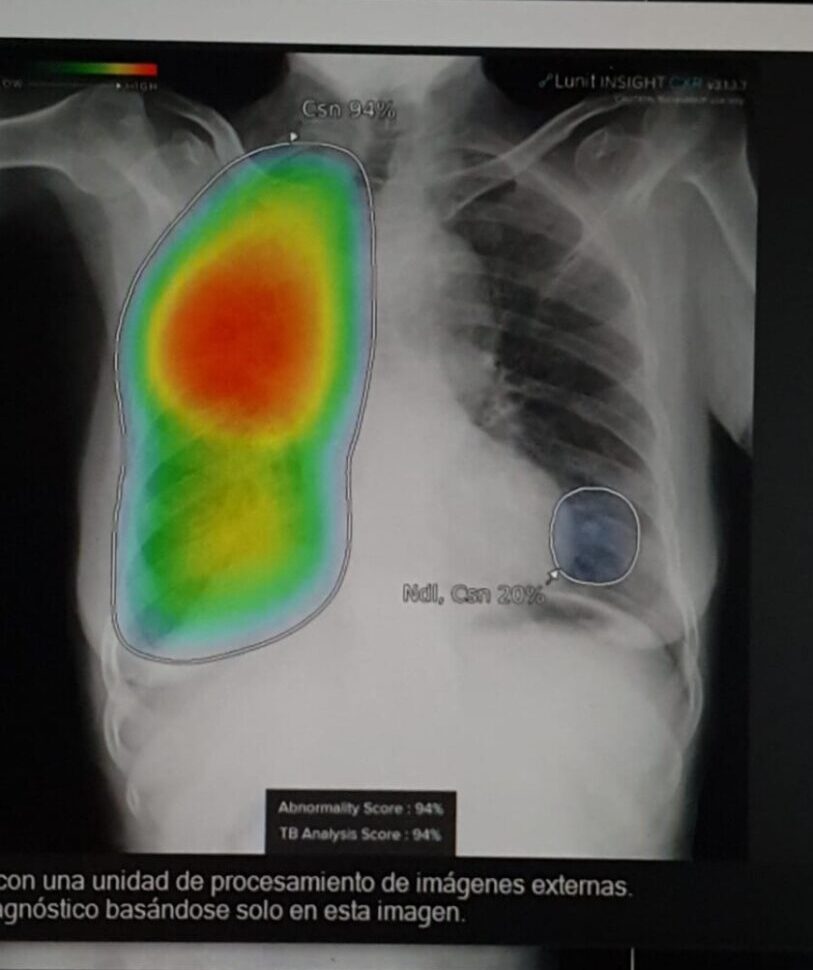

Cabe destacar que se ha utilizado programas informáticos de detección asistida por computadora para la interpretación automatizada de radiografías de tórax para el tamizaje y triaje de la tuberculosis.

Si bien la radiografía del tórax se utiliza ampliamente en la evaluación clínica de la tuberculosis, la variabilidad entre quienes interpretan las imágenes es considerable, y el acceso a radiólogos capacitados es limitado en muchos entornos de escasos recursos. En los últimos años han llegado al mercado programas de detección asistida por computadora para automatizar la interpretación de imágenes digitales de radiografía de tórax y generar una puntuación numérica que indica la probabilidad de tuberculosis.

La exactitud de diagnóstico y el desempeño general de los programas informáticos de detección asistida por computadora son similares a la interpretación de las radiografías digitales del tórax por parte de un lector humano, tanto en el contexto de tamizaje como de triaje.